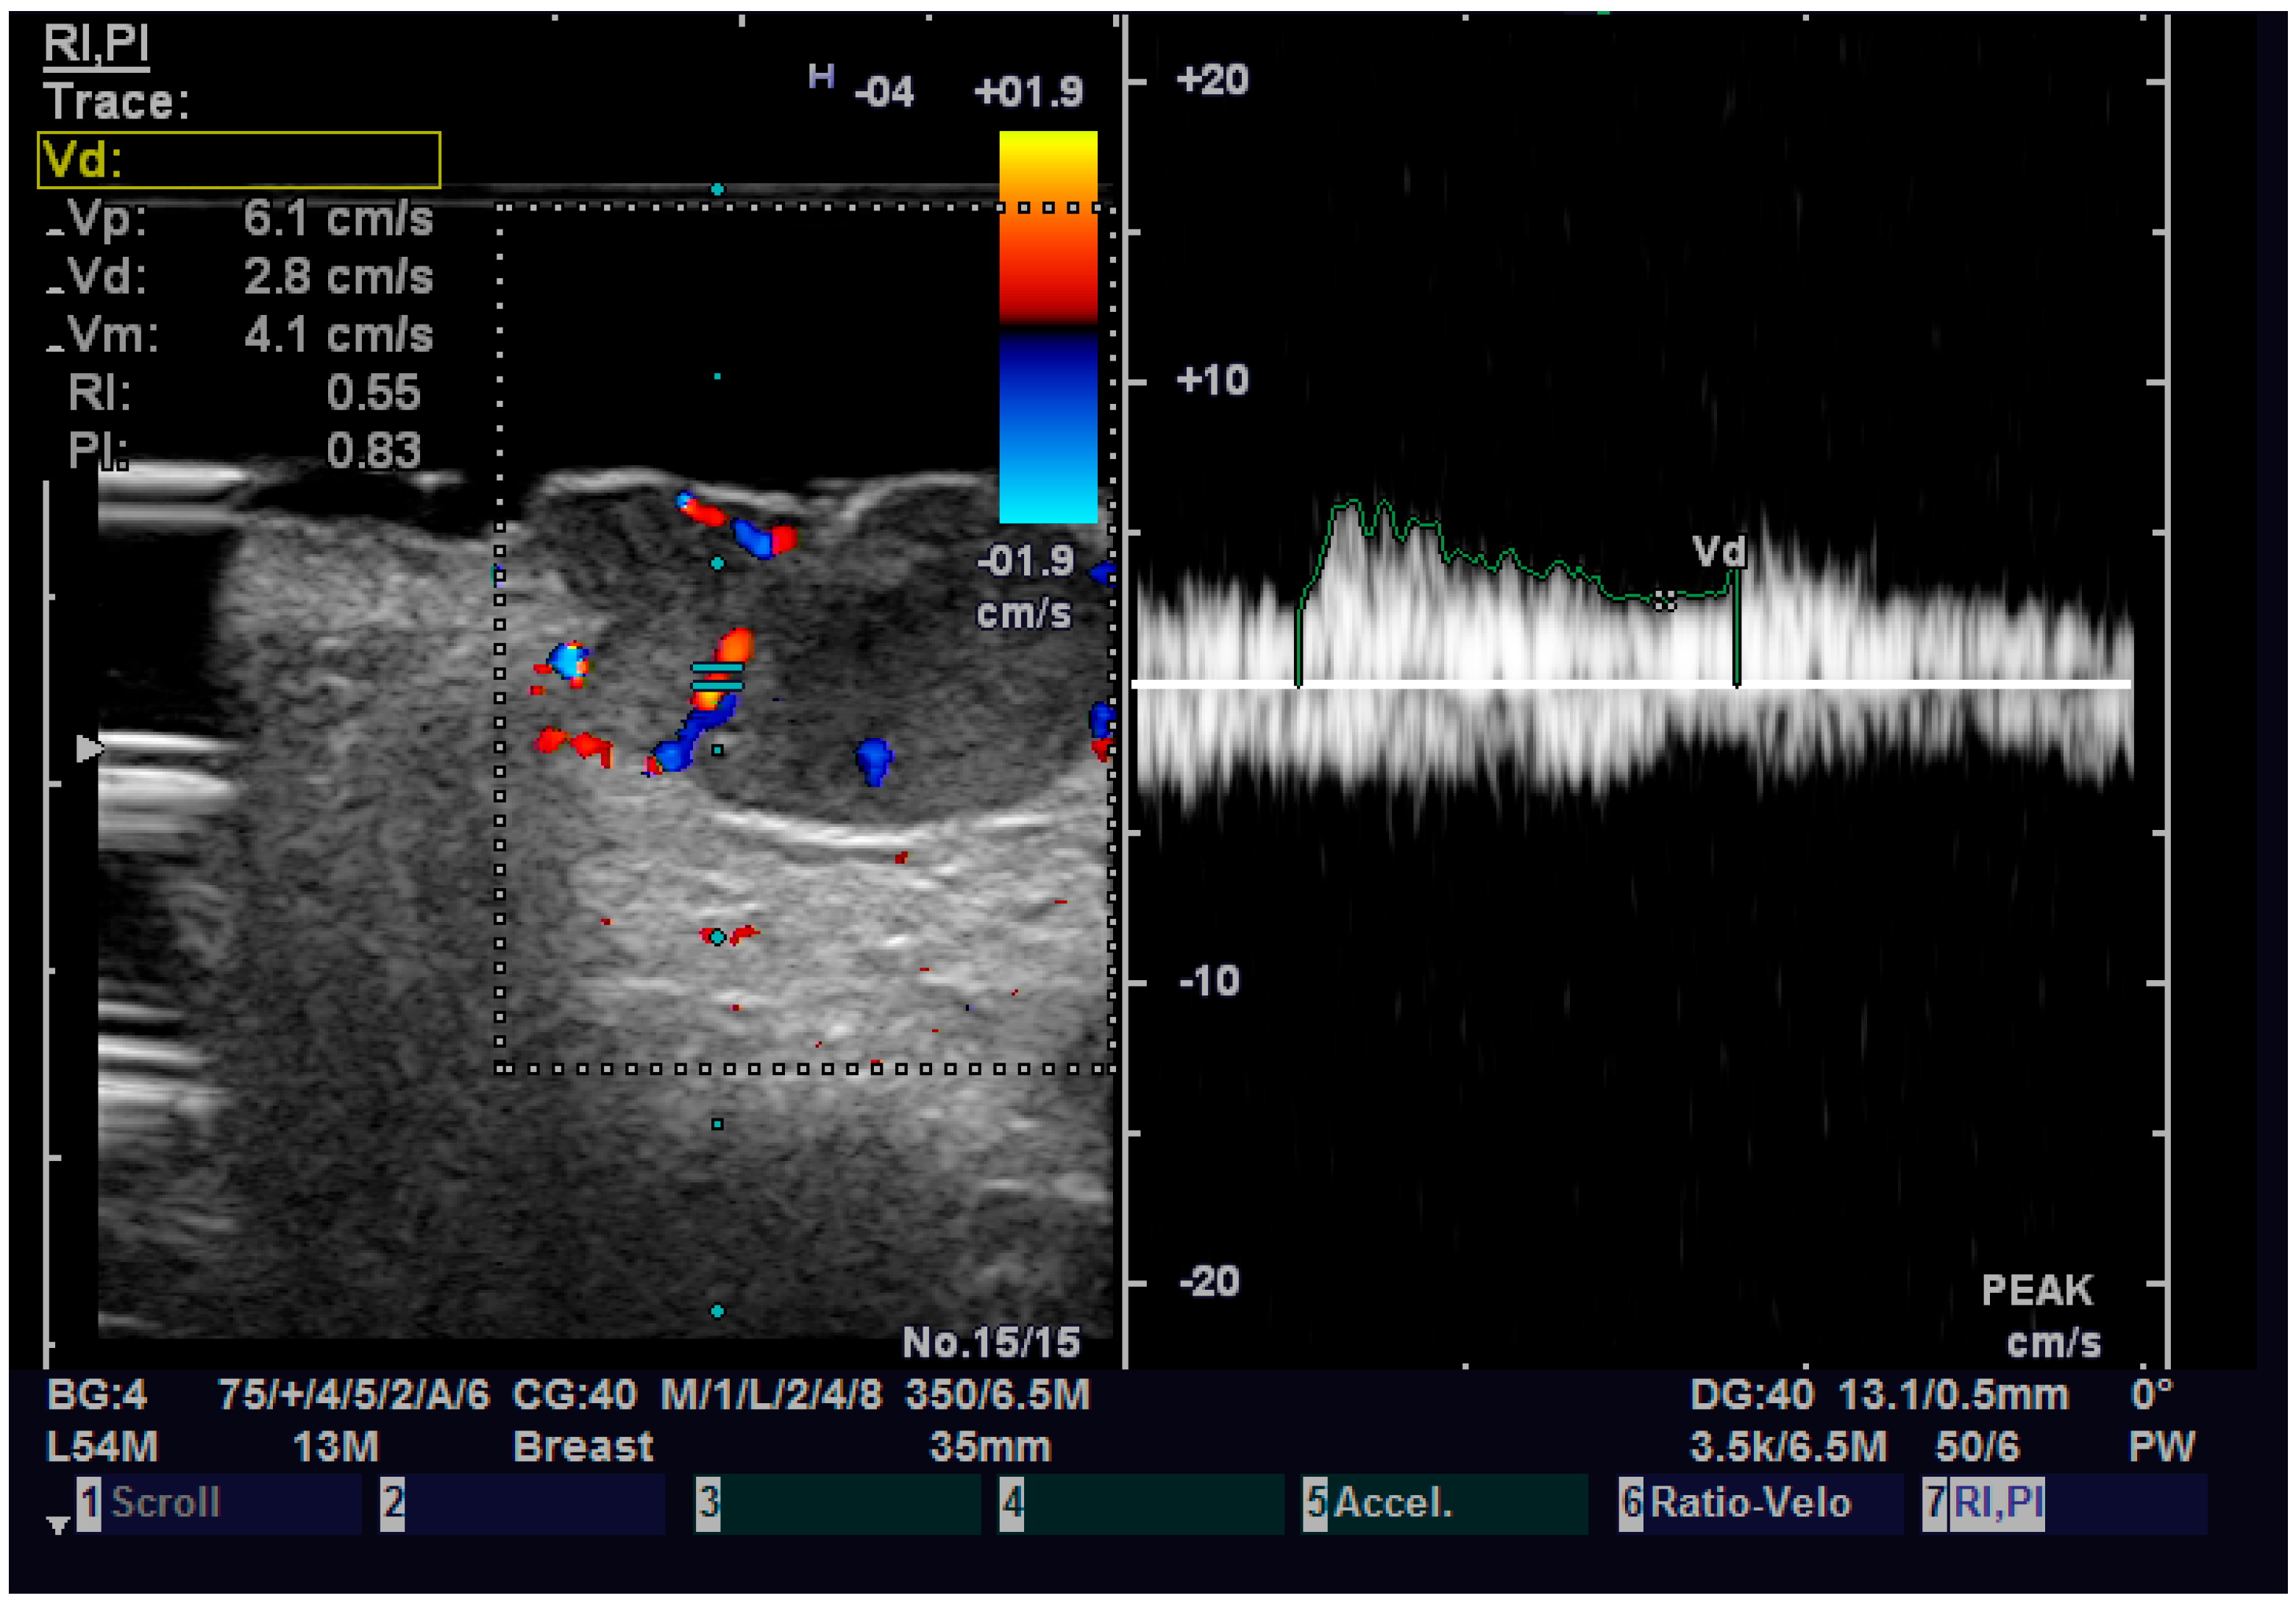

Regarding elastography, we can easily see that the tumor tissue is stiffer than the normal adjacent one (Figure 6). We did not find any significant statistical association between the value of strain ratio and the histology of the tumor. The values in the BCC group were also lower than in the SCC group (95% CI −2.98–0.35, p = 0.126). Doppler examination (Figure 7) showed increased values for both systolic and diastolic speed in the SCC group, but the results were not statistically significant and no association between the type of histology and vascularization was found (Table 4).

Figure 7.

Doppler examination of a SCC.

The strain value in strain elastography serves as a proximate indicator of tissue stiffness or elasticity. Variable skin layers have different elastic qualities, with subcutaneous tissue being more elastic and the epidermis and dermis being less elastic. Increased marginal stiffness is very suggesting for cancer. The malignant tissue develops a fibrotic environment that makes it stiffer than the surrounding tissues [36,37]. Some researchers came to the conclusion that elastography is a variable evaluation that, when combined with B-mode results, may provide the physician or the surgeon with important knowledge regarding different subtypes of BCC. More specifically, infiltrative and non-infiltrative cutaneous basal cell carcinomas are distinguished by enhanced marginal stiffness [38]. Tanaka et al. showed that the tumor thickness of nodular BCC determined by elastography corresponded better with the histological thickness than the tumor thickness measured by traditional B-mode sonography. These results suggest that elastography can be a dependable approach for planning future surgical safety margins since the infiltrative variety of BCC carries a greater risk of recurrence [39]. We did not find any correlation between the nodular or infiltrative type of NMSC and the stiffness of the tumor. We also did not try to measure the thickness of the tumor on elastography, so we cannot confirm the previous result. A certainty that we observed is that the increased stiffness of the tumor compared with the normal adjacent one, which can help us establish the diagnosis of malignant tumor and guide us in surgical treatment.